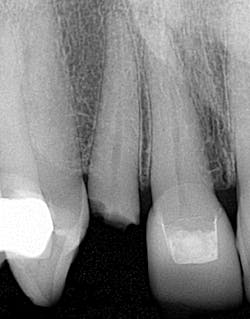

• I have prepped crowns on insufficient tooth structure and then the patient came back six months later with crown in hand (figure 3). It’s one of those moments when you realize a pin and a buildup just weren’t enough. Perhaps a post would have been helpful. I also could have told the patient that he needed to look at alternative treatment options. Now, when I am in those situations, I take a photo of the tooth, show the patient, and tell them what I can and can’t do with the tooth. Patients may not want to hear that their tooth needs to be pulled, but in the long run it’s better for everyone involved.